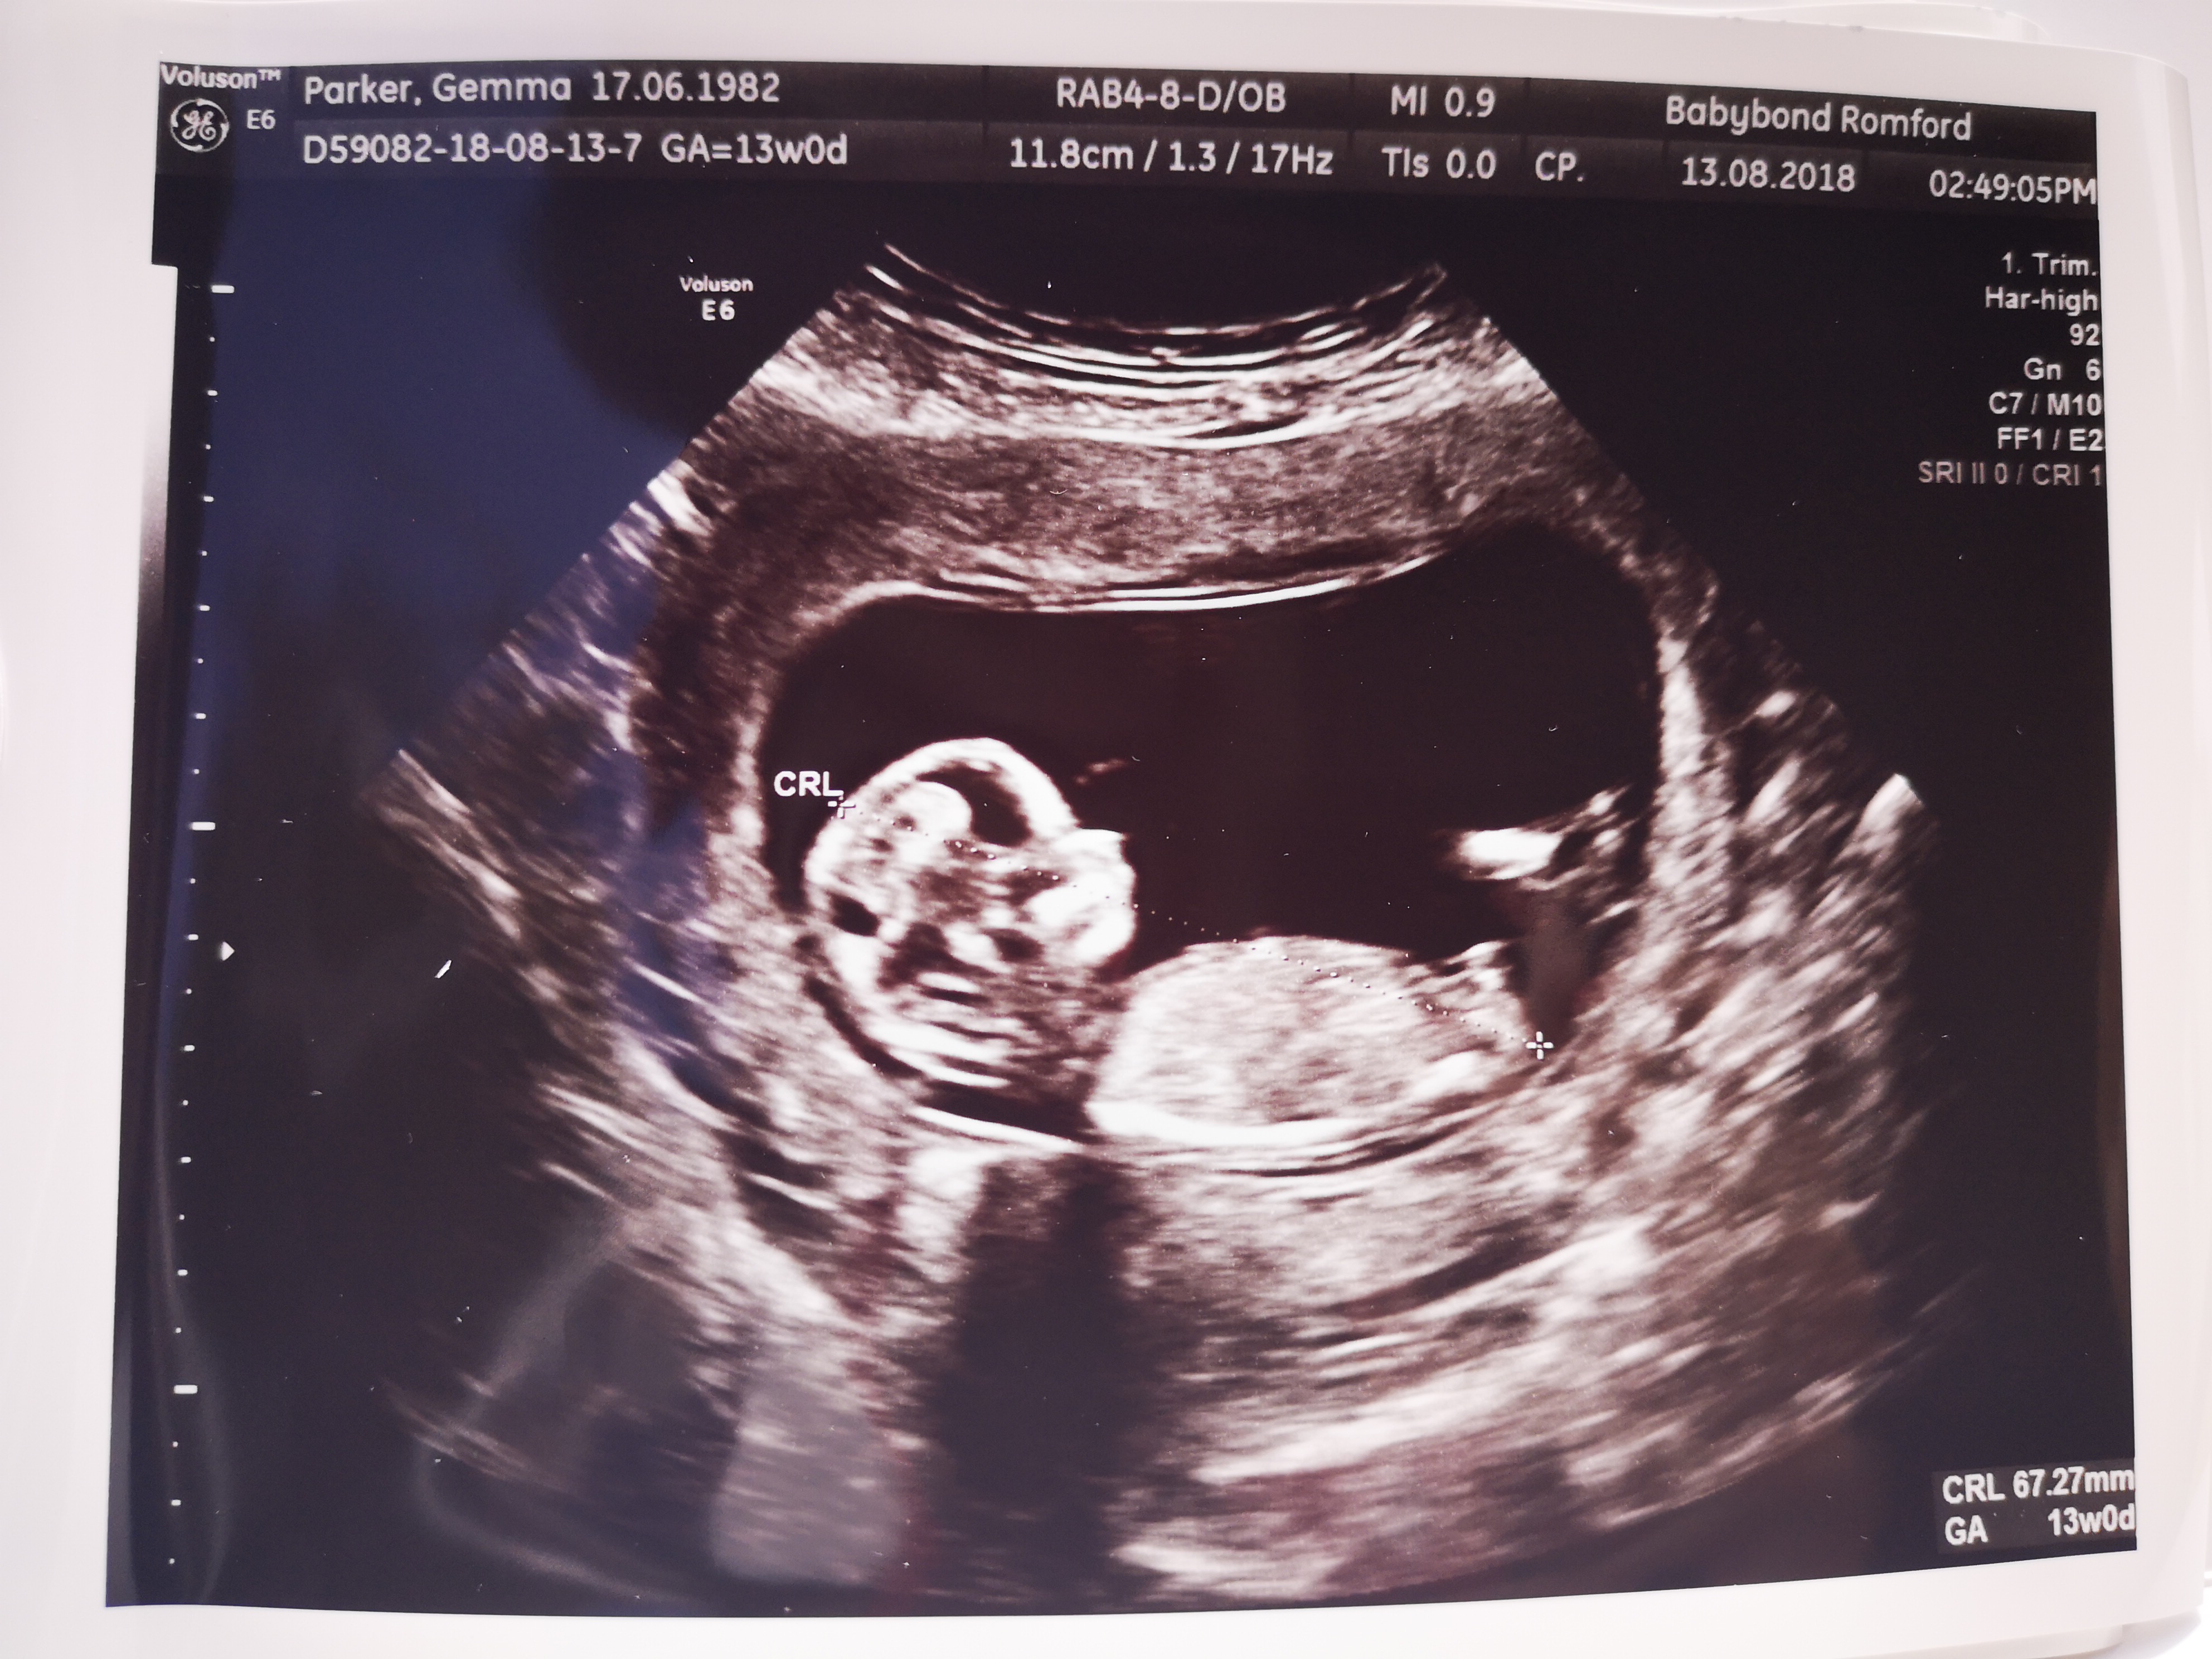

I’m no expert but going to guess boy. Congratulations x

Boy

Boy guess xx

Boy guess from me as well :happy:

Boy guess too

That's definitely a very boy looking nub. :)

Agree. Thinking boy!!!

Boy guess :D